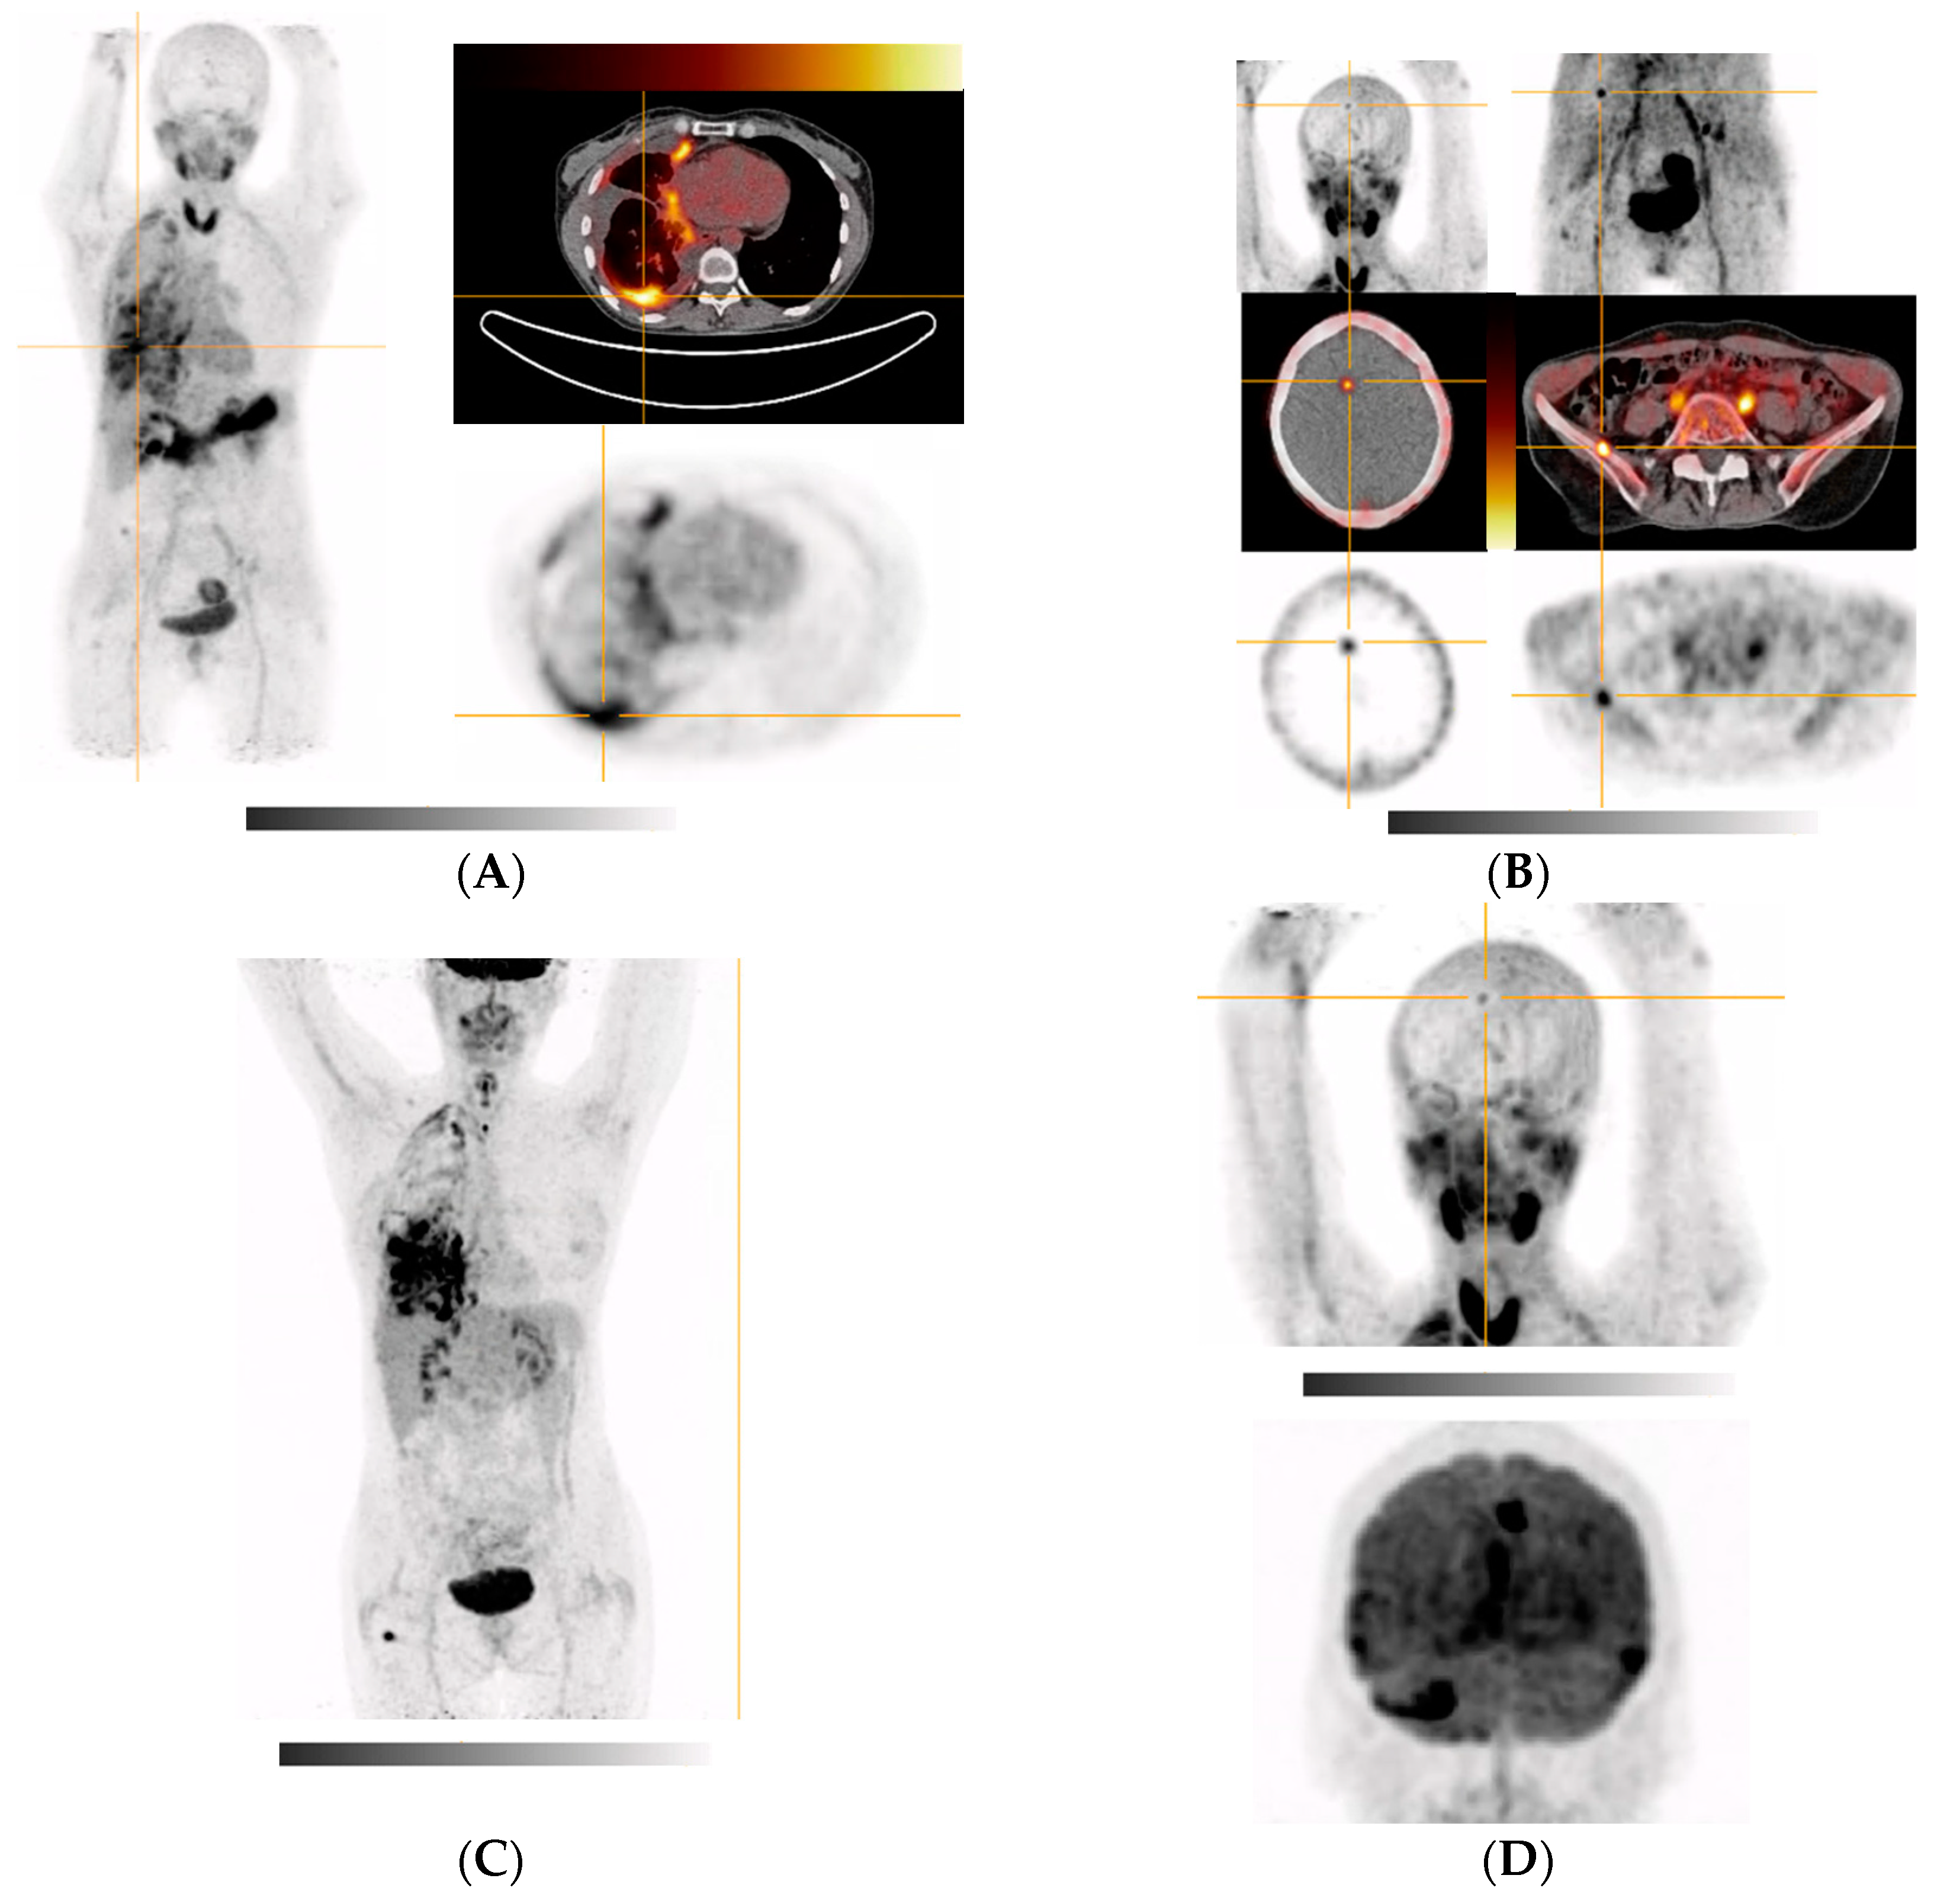

| 6 (Figure 5A,B) | Poorly differentiated NSCLC of right lower lobe (pleural, cerebral, hepatic, and osseous metastases) | VATS with partial pleurectomy and talc pleurodesis | Right hemithorax and right lung, diffuse cerebral (mainly focal in the right frontal cortex in the region of the great longitudinal fissure and periventricular), right and right ilium, left sacrum, right thigh (after surgical removal of a hibernoma), uterus (possible myoma) FDG-PET (Figure 5C,D): whole right hemithorax (especially basolateral, in the myelon, intracranially in the area of the meninges, (around the temporal poles and on the tentorium), in the right frontal cortex in the area of the great longitudinal fissure, right thigh (after surgical removement of a hibernoma) |